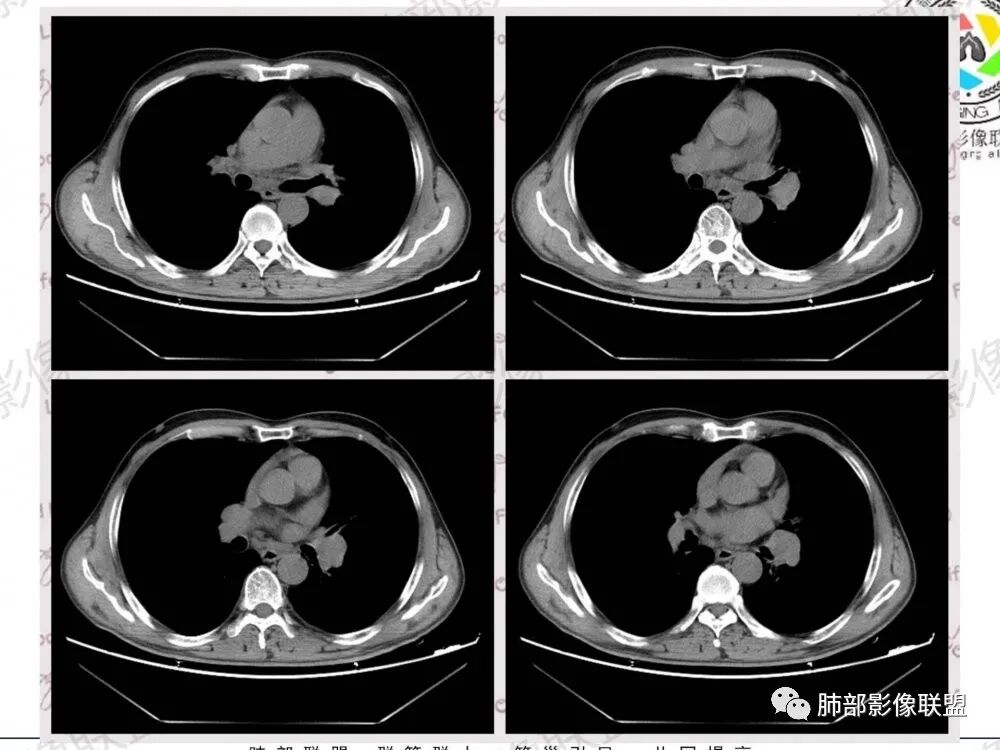

57岁男性,长期吸烟史,有血吸虫病史,有粉尘接触史。发现纵隔淋巴结肿大2年,声嘶伴咳嗽咳痰半月。两年前胸部CT见左上肺尖后段结节并肺门淋巴结肿大,治疗后左上肺结节消失。目前胸部CT:肺气肿,左上肺尖后段见条索影(原来结节治疗后的改变?),肺门、纵隔淋巴结肿大并融合,似见薄壁包膜样强化。考虑淋巴结结核可能性大,注意鉴别淋巴瘤、转移、结节病等。

病史两年,左肺病变治疗后有吸收,需要结合老片对比,有血吸虫,粉尘史,纵隔及肺门淋巴结肿大,淋巴结形态消失,部分融合,周围血管挤压,增强后环形强化,肺内可见多发肺气肿,左肺尖可见纤维索条影(可能既往有陈旧性结核),综合考虑:一元论:结核(纵隔淋巴结及左肺都是结核),二元论:肿瘤性病变合并左肺结核(纵隔淋巴瘤,如果是小细胞肺癌的这么大淋巴结,肺内病灶没有转移,有点奇怪)

纵膈及左肺门多发肿大淋巴结,部分融合呈团块状,密度不均,增强后轻度边缘强化,考虑转移,鉴别淋巴结结核

位移:

纵隔及左肺门多发肿大淋巴结,融合团块状,密度不均,增强后轻度边缘强化,中央似有坏死,考虑转移瘤,鉴别淋巴瘤

中老年男性,长期吸烟,肺气肿明显,发现纵隔淋巴结两年了,声音嘶哑,病灶压迫喉返神经了?喉部有占位吗?左肺尖小片状病灶,周围多发长条纤维牵拉,胸膜增厚,纵隔及左肺门多发肿大淋巴结,增强后显示淋巴结融合且坏死明显,薄环状强化。如果是恶性肿瘤,小细胞癌或者鳞癌,肺内病变应该增大增多了;一元化我考虑纵隔淋巴结结核,左肺尖结核灶。

1.左肺门及纵隔见异常增大淋巴结,部分融合,不均匀轻度强化,未见明显坏死。

肿大淋巴结与纵隔血管等结构“无缝”贴合。

2.纵隔增宽但依旧居中。

2、小细胞癌恶性程度高,发展迅速,转移发生早;常有纵隔淋巴结的明显增大融合(发生率达96.5%),呈“冰冻纵隔”,淋巴转移常为逐站的连续性转移;亦有血行转移,脑、肾上腺、肝、胰、骨髓等;转移灶常比原发灶大得多,即“娘小崽大”特点;